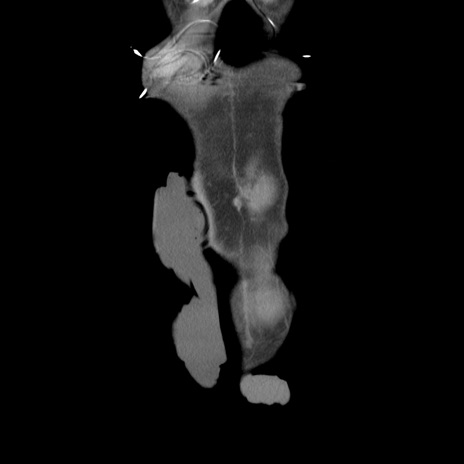

症例11(冠状断像)

【症例】 60歳代男性

【主訴】 下腹部痛

【現病歴】 本日夜中より下腹部痛の症状認め、受診。

【既往歴】 膀胱癌(膀胱全摘+尿管皮膚瘻術) 、胃癌術後

【身体所見】 BT 35.3℃、PR 58/min、BP 136/98mHg、腹部平坦、軟、腸蠕動音±、ストマ留置あり、左上腹部~正中部に圧痛あり、反跳痛なし。

【データ】WBC 5100、CRP0.01